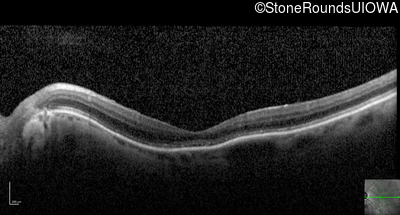

Optical Coherence Tomography - Right - 20/200

Exemplar / OCT Stack